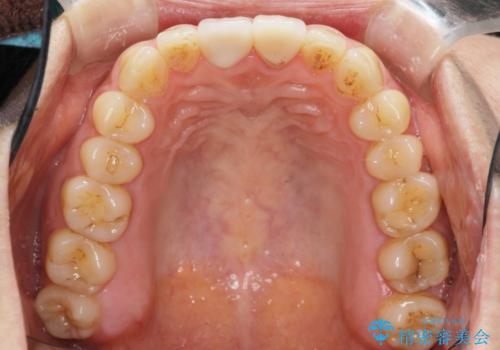

- 右上の前歯が折れたことを主訴に来院された患者様です。

歯が折れた部分は他院により応急処置で仮止めされていました。

欠けた範囲が大きかったため、セラミッククラウンによる補綴治療を行いました。

※左上の前歯(外国で治療されたとのこと)の失活が疑われたためそちらの治療も提案しましたが、ご希望されませんでした。